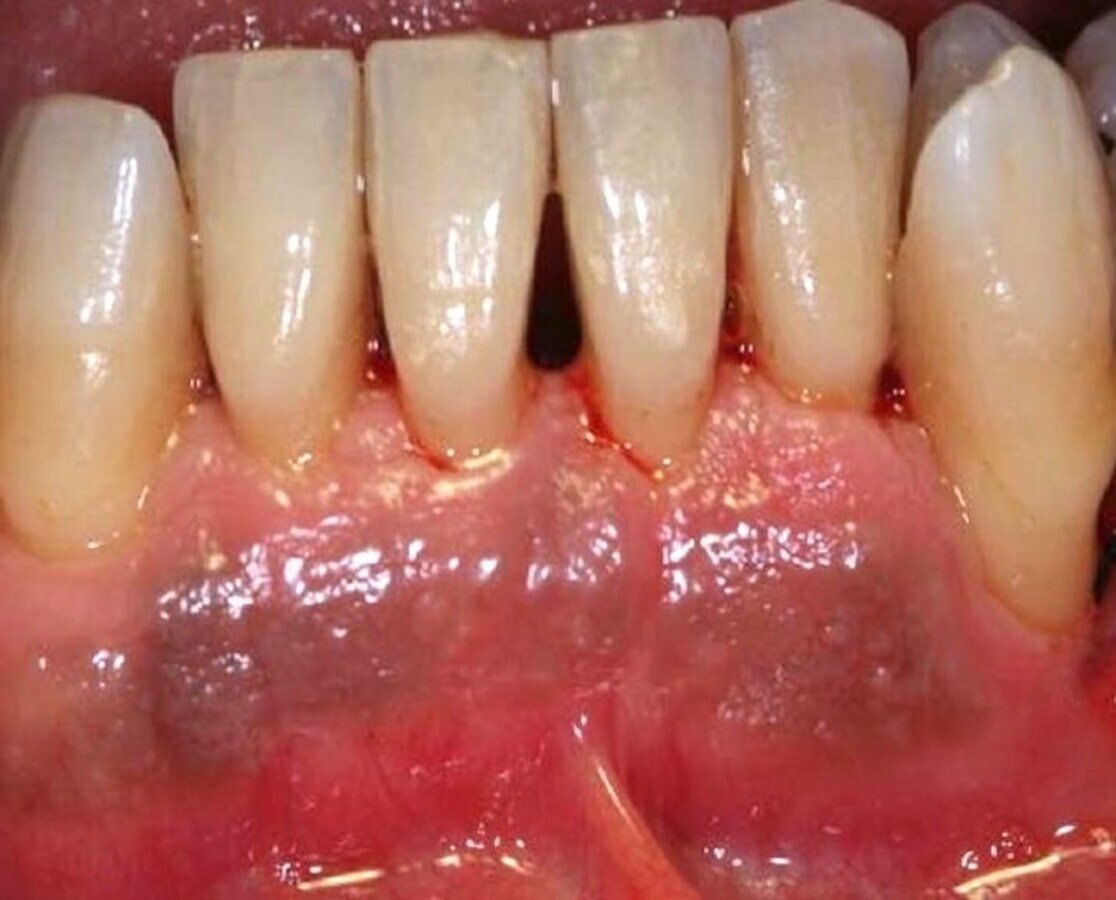

Por otra parte, sabemos que independientemente de la técnica o del instrumental utilizado, algunos tratamientos pueden tener aparejados efectos no deseados. En el caso del raspado, alisado y pulido radicular, además de los efectos “deseados”, también se generan otros “indeseados” como la hipersensibilidad dentinaria. El láser es un buen complemento para reducir o eliminar consecuencias indeseadas como la hipersensibilidad (Figura 4). De hecho, la aplicación del láser para la hipersensibilidad es más eficaz que otras técnicas, tanto al finalizar el tratamiento como al mes y a los 6 meses4. Kimura y colaboradores, en una revisión bibliográfica de casi 15 años, concluyeron que la eficacia del tratamiento de la hipersensibilidad utilizando láser era mayor que con otras técnicas5.

Figura 4. El láser reduce o elimina consecuencias indeseadas del tratamiento como la hipersensibilidad.

El uso del láser como refuerzo del tratamiento convencional es cada vez más común. Un buen ejemplo de ello es el uso de la fotobiomodulación (antes llamada bioestimulación) en el tratamiento de la enfermedad periodontal (Figura 5), que es muy utilizada debido a que acelera la cicatrización de las heridas y a sus propiedades analgésicas, antiinflamatorias y antiedematosas.

Cuando se complementa el tratamiento convencional con la fotobiomodulación lumínica, se acorta su duración y se consigue eliminar el dolor más rápido que solo con el tratamiento convencional. Asimismo, la reducción de la profundidad de la bolsa periodontal en las visitas sucesivas es estadísticamente mayor en el grupo tratado con láser que en el grupo control, siendo esta reducción aún mayor en las bolsas más profundas6.